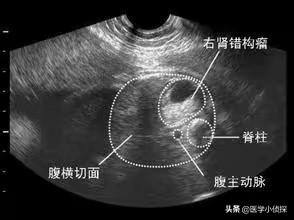

第三,刚肾脏彩超检查发现说是错钩瘤,结果一转头做CT检查又说是小囊肿,这到底是回事?

实际上,这在临床上并不罕见!这是检查手段问题,尤其是当肾脏出现的囊肿比较小时候,容易混淆。当然,小囊肿的观察,B超看起来会相对比较准确,但任何一项检查准确性还与检查者能力水平有关!

但不管是错构瘤,还是肾囊肿,大家都不用担心,都是良性的。肾错构瘤也是一种占位,但它属于脂肪瘤一种,也被称之为肾血管平滑肌脂肪瘤,是一种先天发育障碍,同肾囊肿一样,没有压迫、没有症状等不需要进行处理,定期体检观察即可!